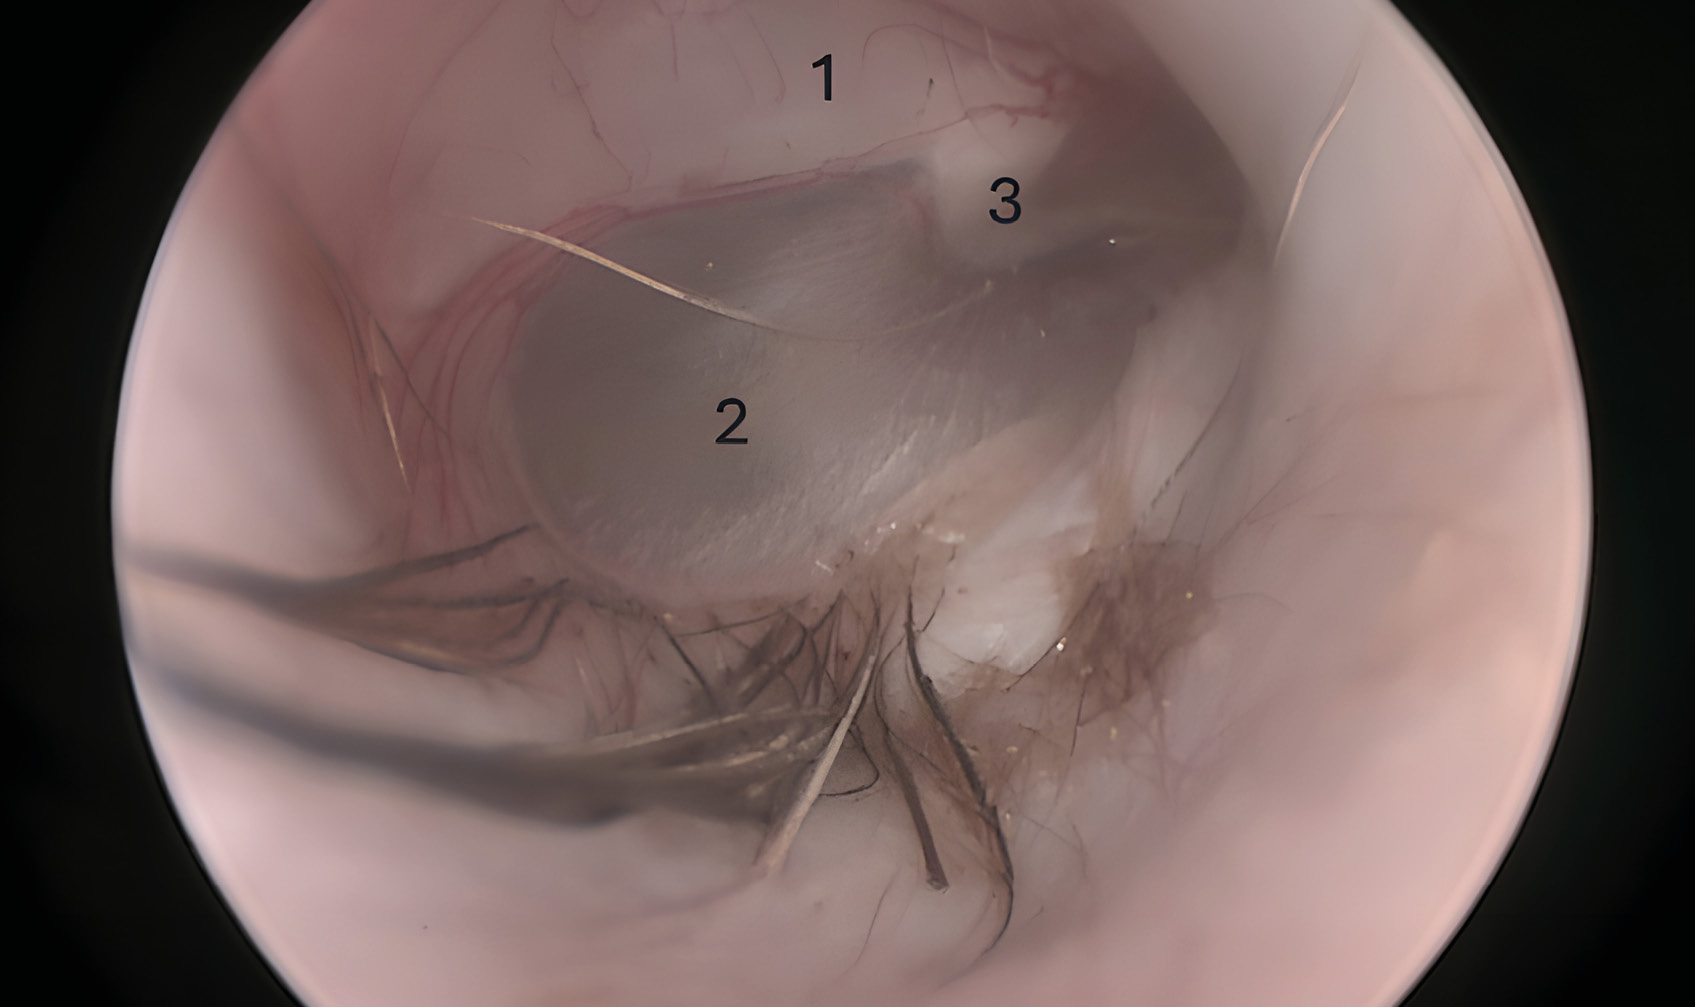

La membrana timpánica consta de dos secciones: la pars flaccida (más pequeña) dorsalmente y la pars tensa (más grande) ventralmente. En la superficie medial de la pars tensa se inserta el manubrio del hueso martillo, que se visualiza externamente como la estría del martillo (estria mallearis) (imagen 1).

Miringotomía

La miringotomía es la incisión quirúrgica de la membrana timpánica, que permite acceder al oído medio para la toma de muestras, el lavado y la aplicación de terapia tópica (imagen 6). Esta técnica está indicada siempre que exista evidencia clínica de otitis media, anomalías de la membrana timpánica o hallazgos anormales en las imágenes diagnósticas (TC, RMN) del oído medio. Se deben recolectar muestras para investigación citológica y cultivo, y posteriormente limpiar y secar el oído externo. Este procedimiento debe realizarse bajo anestesia general inhalatoria y con un videotoscopio de fibra óptica para mejorar la visualización y reducir el riesgo de complicaciones. La incisión de la miringotomía debe realizarse en el cuadrante caudoventral de la membrana timpánica (pars tensa) utilizando una sonda urinaria de tamaño adecuado para recolectar muestras e irrigar la cavidad del oído medio.

En el caso de los pacientes felinos es posible el acceso al compartimento ventromedial de la bulla timpánica, tras la miringotomía y fenestración del septo de la bulla (imagen 7).